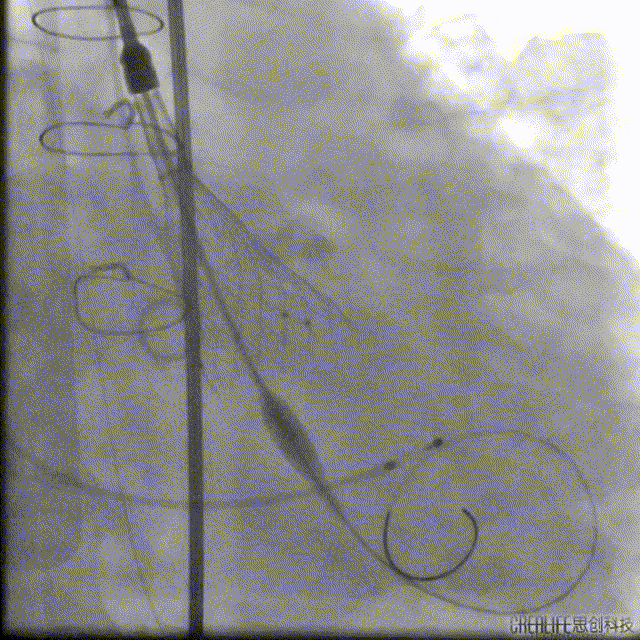

解剖上,这个患者虽然是右无融合的二叶瓣,但是右窦发育较小,形态上接近0型二叶瓣,瓣上钙化中,且集中在左窦,接近左右瓣叶联合部。瓣环及流出道平面较大,而瓣上结构较小,瓣叶联合部距离只有26,这种情况下只能考虑根据瓣上结构进行选择瓣膜。目标瓣膜为26号,为了避免破坏瓣上结构,我们选择26瓣膜的下限20号瓣膜进行与扩张。因为主动脉弓和升主动脉角度问题,没有选择plus。20球囊扩张可以看到左窦钙化很硬,右无联合可以推开,没有反流,故选择26号瓣膜,高位释放。释放后瓣膜下滑到标准位,有明显的腰,故用20球囊进行后扩展。最后造影虽然有中度瓣周漏,但是考虑患者狭窄解除,且升主动脉人工血管限制了瓣膜的流出端,未再行瓣中瓣。术中撤除ECMO,辅助循环约1小时。

术后:

患者跨瓣压差消失,轻中度瓣周漏,ECMO成功撤机后转入CCU,6天后转入普通病房,出院前超声显示EF值已提升为40%,患者症状改善,随后出院。